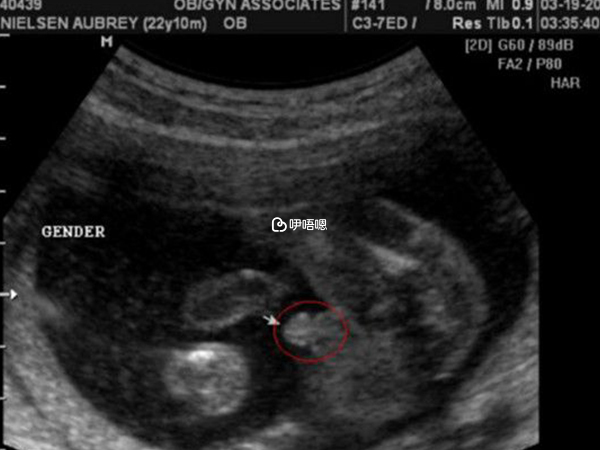

女性懷孕後,據說可以通過B超單子看生男生女,通常在孕婦懷孕三個月以後,男胎和女胎生殖器官開始分化,在B超檢查時下半身影像並不一樣,從超聲影象上來看,男孩和女孩最明顯的區別,就是生殖器官不一樣,下面這張B超影象,代表懷的是男孩。

圖片可以看到有突出的東西,也就是小雞雞的圖片很清晰,這是男胎最明顯的標誌,如果是女孩的話,可能看不到突出的一些東西,反而會看到明顯的三條白線,這是女寶寶非常明顯的標誌,這是男孩和女孩的區別。

3、懷男孩小雞b超圖片分享